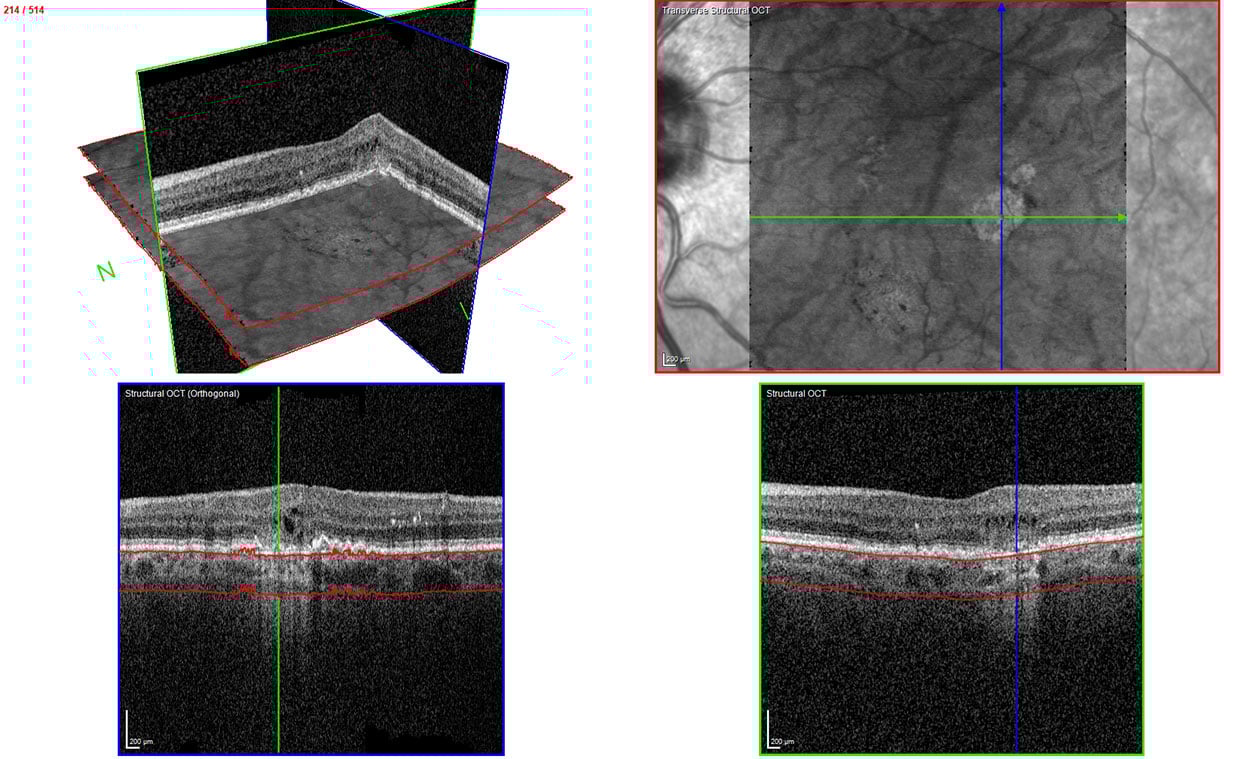

The transverse section or en-face OCT image option provides a unique visualization of RPE and photoreceptor structure, adding complementary information relating to the distribution of pathological change within the posterior segment. One characteristic of GA is choroidal hypertransmission defects, a “window” defect through the RPE associated with nascent GA (nGA) and cRORA, providing a complementary alternative to autofluorescence images.

Image 3: Transverse section OCT – choroidal hypertransmission defect recorded with SPECTRALIS